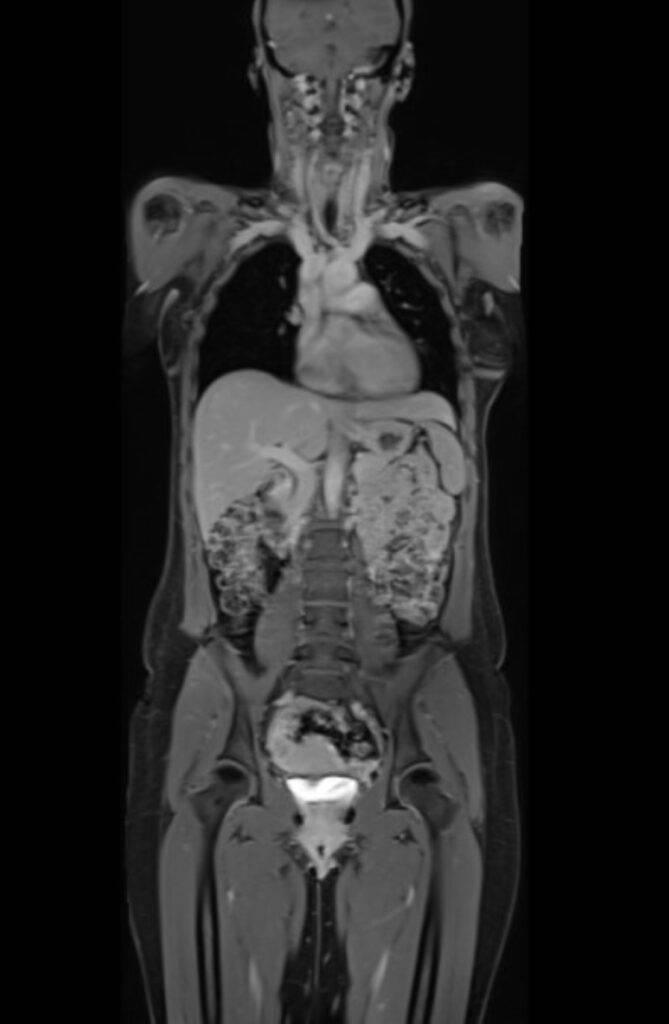

Eine Ganzkörper MRT liefert hochauflösende Bilder des gesamten Körpers von Kopf bis Fuß und ist daher ideal für Vorsorgeuntersuchungen oder zur Verlaufsbeurteilung von malignen Erkrankungen:

- Wurde bereits eine Tumorerkrankung diagnostiziert, kann die Ganzkörper MRT nützlich sein, die momentane Ausbreitung präzise zu beurteilen. Auch Fernmetastasen können durch eine Ganzkörperuntersuchung frühzeitig festgestellt werden. Die MRT ist aufgrund des höheren Weichteilkontrasts speziell in den Organen des Oberbauchs, der Lymphknoten, des Gehirns und des gesamten Skelettsystems hochpräzise bei der Erkennung von Metastasen.

- Auch zur Verlaufsbeurteilung und zur frühzeitigen Erkennung von Rezidiven bei malignen Erkrankungen eignet sich die Ganzkörper MRT hervorragend.

- Mittels einer MRT des ganzen Körpers lassen sich zudem entzündliche Skeletterkrankungen wie z.B. die rheumatoide Arthritis feststellen. Da sowohl kleinste Gelenke der Extremitäten als auch die großen Gelenke des Rumpfes betroffen sein können, ist eine Ganzkörper MRT besonders aussagekräftig.

Die Ganzkörper-MRT stellt eine besonders detaillierte Methode in der medizinischen Bildgebung dar, die es ermöglicht, ohne die Verwendung ionisierender Strahlung, das Innenleben unseres Körpers umfassend zu visualisieren. Mittels starker Magnetfelder und Radiowellen wird der Körper in Gänze erfasst, wodurch ein vollständiges Bild der verschiedenen Organsysteme, der Gefäße sowie der Weichteile des Bewegungsapparates wie Muskeln, Sehnen und Gelenke ermöglicht wird.

Dank der herausragenden Weichteildarstellung und der Möglichkeit, hochauflösende, detailreiche Bilder zu erzeugen, bietet die Ganzkörper MRT eine unvergleichliche Diagnostik.

Die Technologie erlaubt es, von Kopf bis Fuß ohne jegliche Strahlenbelastung detaillierte Einblicke in den menschlichen Körper zu erhalten und ist somit ideal für eine umfassende Gesundheitsüberprüfung und zur Früherkennung verschiedenster Erkrankungen geeignet. Die MRT Ganzkörper Untersuchung ist ein präzises und umfangreiches diagnostisches Bildgebungsverfahren.